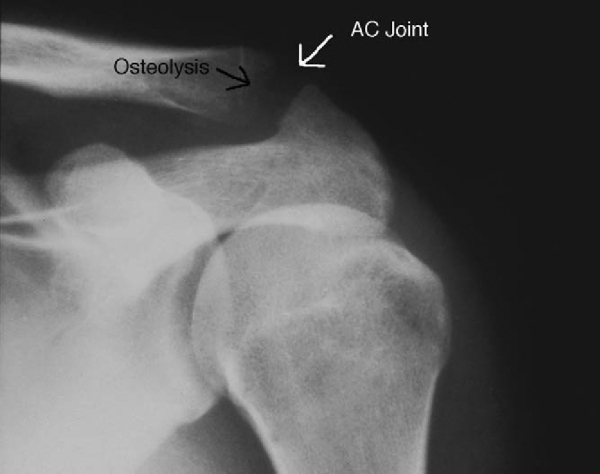

A radiographic series of the shoulder typically includes an anteroposterior radiograph of the glenohumeral joint (30 degrees from anteroposterior of shoulder) to look for glenohumeral arthritis; an outlet view for evaluation of acromial morphologic features (

Fig. 23-1

); an axillary lateral view, which is the best view to rule out an os acromiale (unfused acromion); and a Zanca view, which is the best view for evaluation of degenerative changes or osteolysis of the acromioclavicular joint (

Fig. 23-2

).